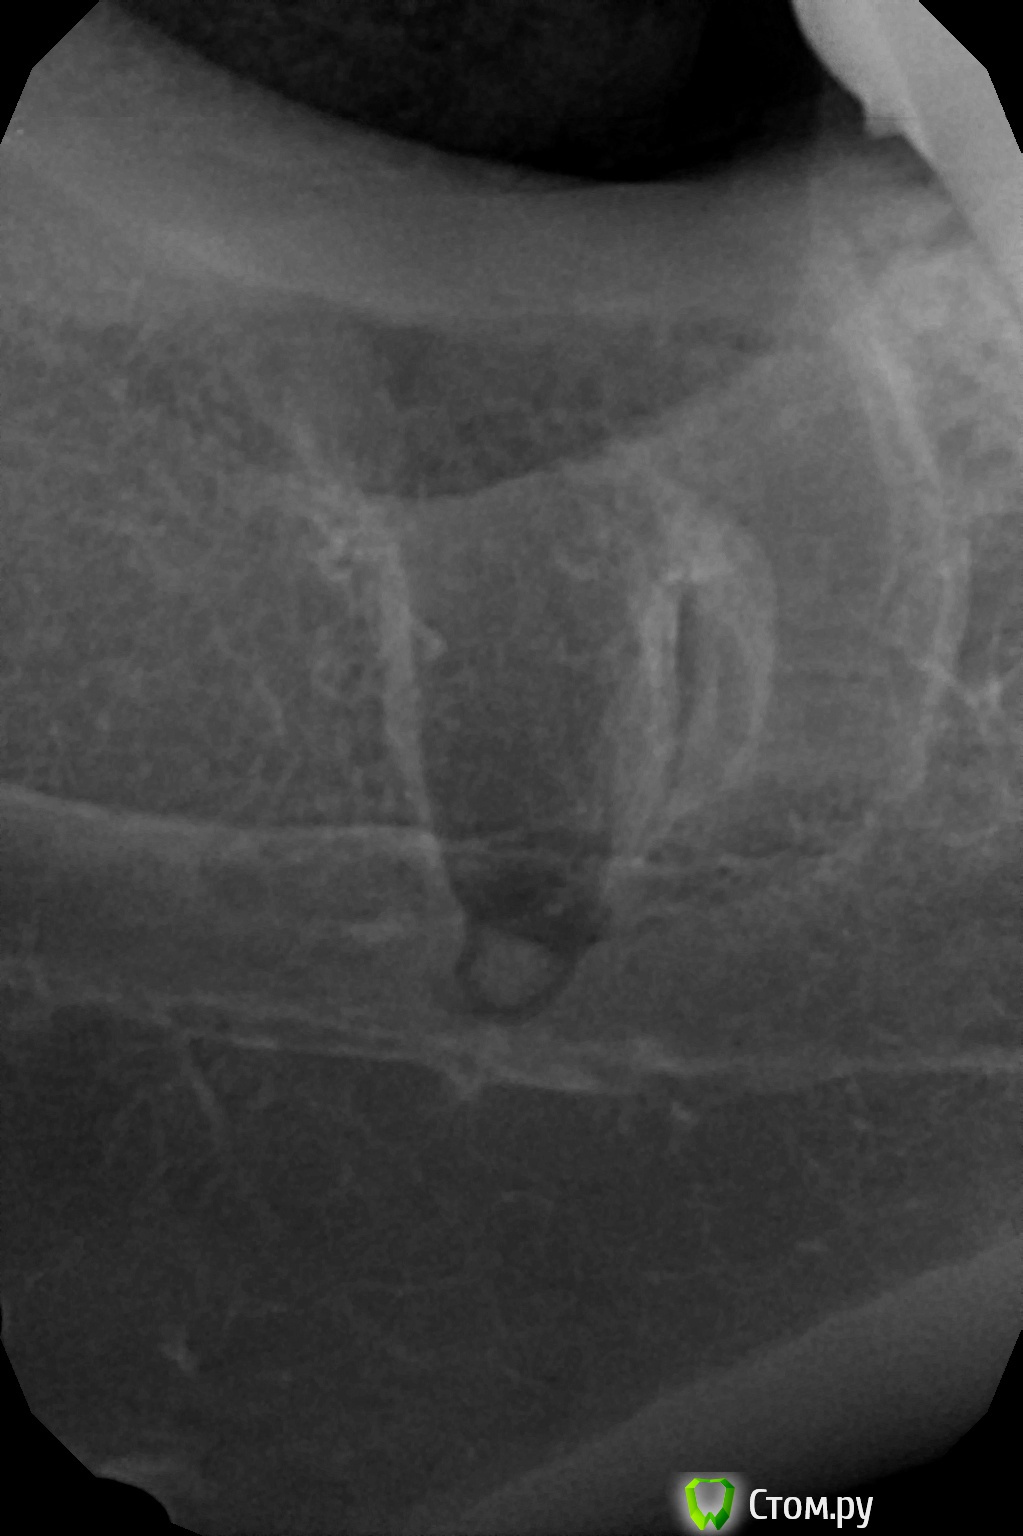

faity Опубликовано 24 сентября, 2014 Поделиться Опубликовано 24 сентября, 2014 пам-пам-парарам, привет чужое ЛПУ)))лунка визуально чистая была, АВ лежала строго в щеку, по результату, без бино вообще не видно 7 Ссылка на комментарий

faity Опубликовано 25 сентября, 2014 Поделиться Опубликовано 25 сентября, 2014 лунка визуально чистая была, АВ лежала строго в щеку, по результату, без бино вообще не видно Каким инструментом убрали . СпсАпекальный элеватор и зонд Ссылка на комментарий

faity Опубликовано 26 сентября, 2014 Поделиться Опубликовано 26 сентября, 2014 Думате была острая необходимость этот апекс убирать? Считается, что до 2 мм иногда можно забыть. Я оставлял раз 5... не видел и/или оооочень близко канал или пазуха.Болел, пух, по показаниям короче 1 Ссылка на комментарий

faity Опубликовано 26 сентября, 2014 Поделиться Опубликовано 26 сентября, 2014 Я бы тоже не трогал, если бы не болел) Ссылка на комментарий

АнтонТЛТ Опубликовано 26 сентября, 2014 Поделиться Опубликовано 26 сентября, 2014 Молодец, что убрал) 2 Ссылка на комментарий